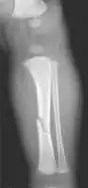

The material factual allegations of the amended complaint are as follows. Plaintiff was born on May 14, 1970. On repeated occasions during the first year of her life she was severely beaten by her mother and the latter's common law husband, one Reyes. On April 26, 1971, when the plaintiff was eleven months old, her mother took her to the San Jose Hospital for examination, diagnosis, and treatment. The attending physician was defendant Dr. Flood, acting on his own behalf and as agent of the defendant San Jose Hospital. At the time, the plaintiff was suffering from a comminuted spiral fracture of the right tibia and fibula, which gave the appearance of having been caused by a twisting force. Plaintiff's mother had no explanation for this injury. Plaintiff had bruises over her entire body. In addition, she had a non-depressed linear skull fracture which was then in the process of healing. Plaintiff demonstrated fear and apprehension when approached. Inasmuch as all plaintiff's injuries gave the appearance of having been intentionally inflicted by other persons, she exhibited the medical condition known as the battered child syndrome.

Landeros presented to the emergency room with a spiral fracture of the tibia, among other injuries.